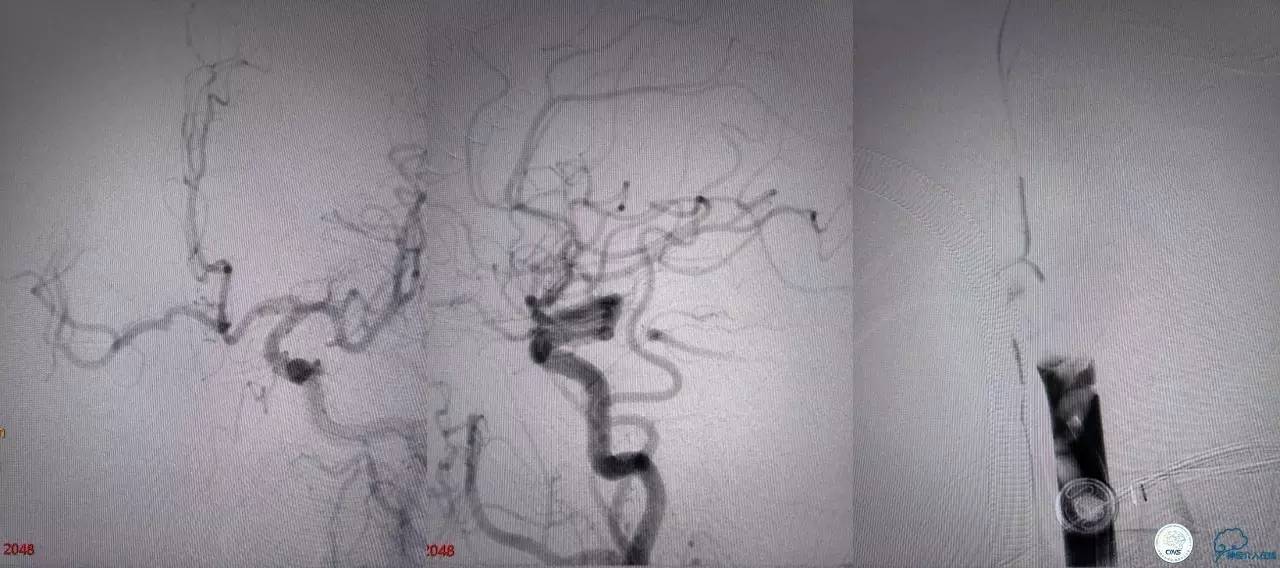

造影结果:右侧颈总动脉远端闭塞,前交通动脉开放,代偿方式:左侧颈内动脉→左侧大脑前动脉A1→前交通动脉→右侧大脑前动脉A1(反向)→右侧大脑中动脉供血区代偿。双侧大脑后动脉、右侧小脑上动脉及基底动脉顶端未见显影。

结合病史,体征及影像学,斟酌患者本次发病为基底动脉尖急性闭塞,发病机制:栓塞?右侧颈总动脉慢性闭塞?非责任血管,且代偿良好,暂时不需处理!

6F导引导管到位至RV2远端,rebar-18微导管及transand微导丝至右侧大脑后动脉P1远端。

solitaireAB4-20mm支架取栓。

基底动脉顶端仍有大量血栓,双侧大脑后动脉未见显影,双侧小脑上动脉再通。再次取栓?还是动脉溶栓?

决定导管内给予替罗非班6ml,复查造影BA顶端仍闭塞,第二次取栓。

第二次取栓后可见基底动脉顶端仍有大量血栓,右侧大脑后动脉开通,但左侧大脑后未见显影且左侧小脑上动脉闭塞!